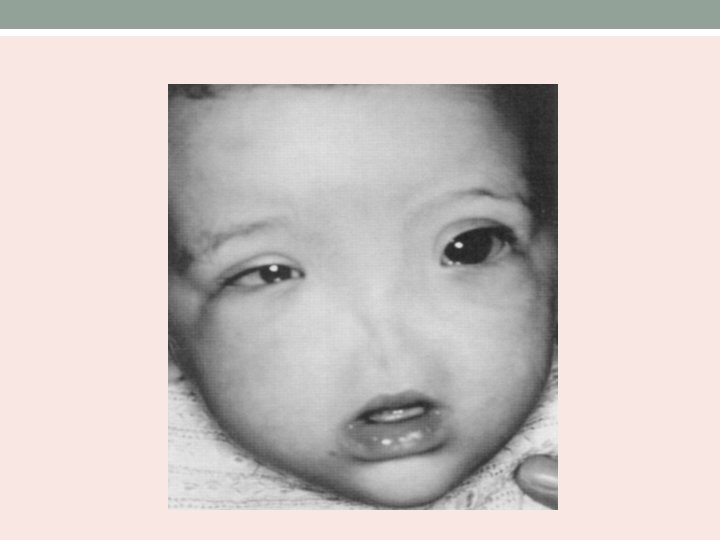

Arhinia • Congenital absence of external nose, nasal cavities and olfactory apparatus. • Associated with anomalies of ocular and CNS. • Nasal placode fails to canalize and form nasal passages.

Clinical presentation • Ranges from hyporhinia to arhinia. • At birth, only depresion present between the eyes. • Respiratory distress and cyanosis while feeding. • Underdeveloped maxilla and high arched palate. • Hypertelorism • Hypernasal speech